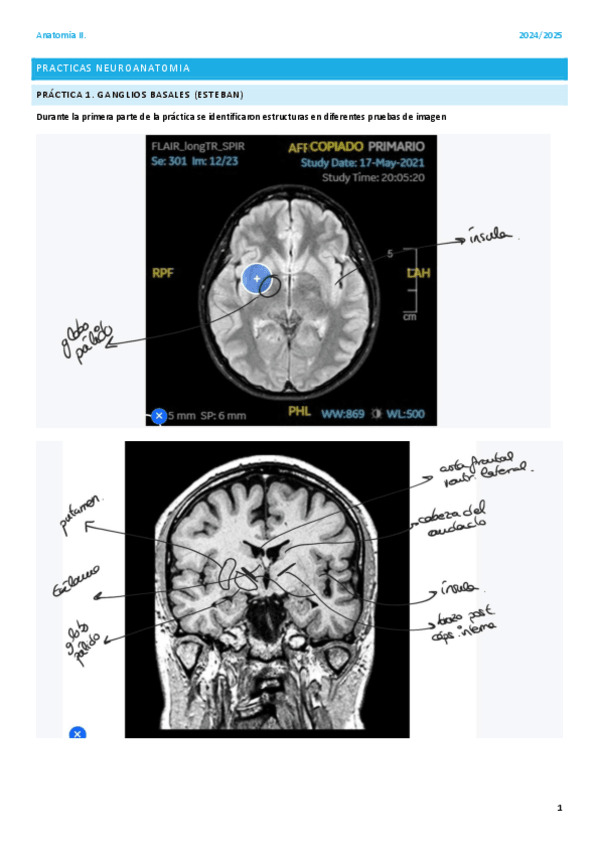

He publicado nuevos apuntes de 2º Anatomía Humana II: practicas-neuroanatomia.pdf

He publicado nuevos apuntes de 2º Anatomía Humana II: practicas-imagenes-resonancias.pdf